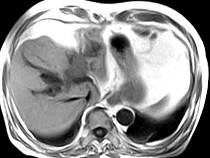

问题 男,43岁,右上腹痛,黄疸,AFP阴性,消瘦乏力,影像检查如下图,诊断为()

选项 A.急性化脓性胆管炎 B.胆管癌 C.脂肪肝 D.原发性肝癌 E.肝血管瘤

答案 B